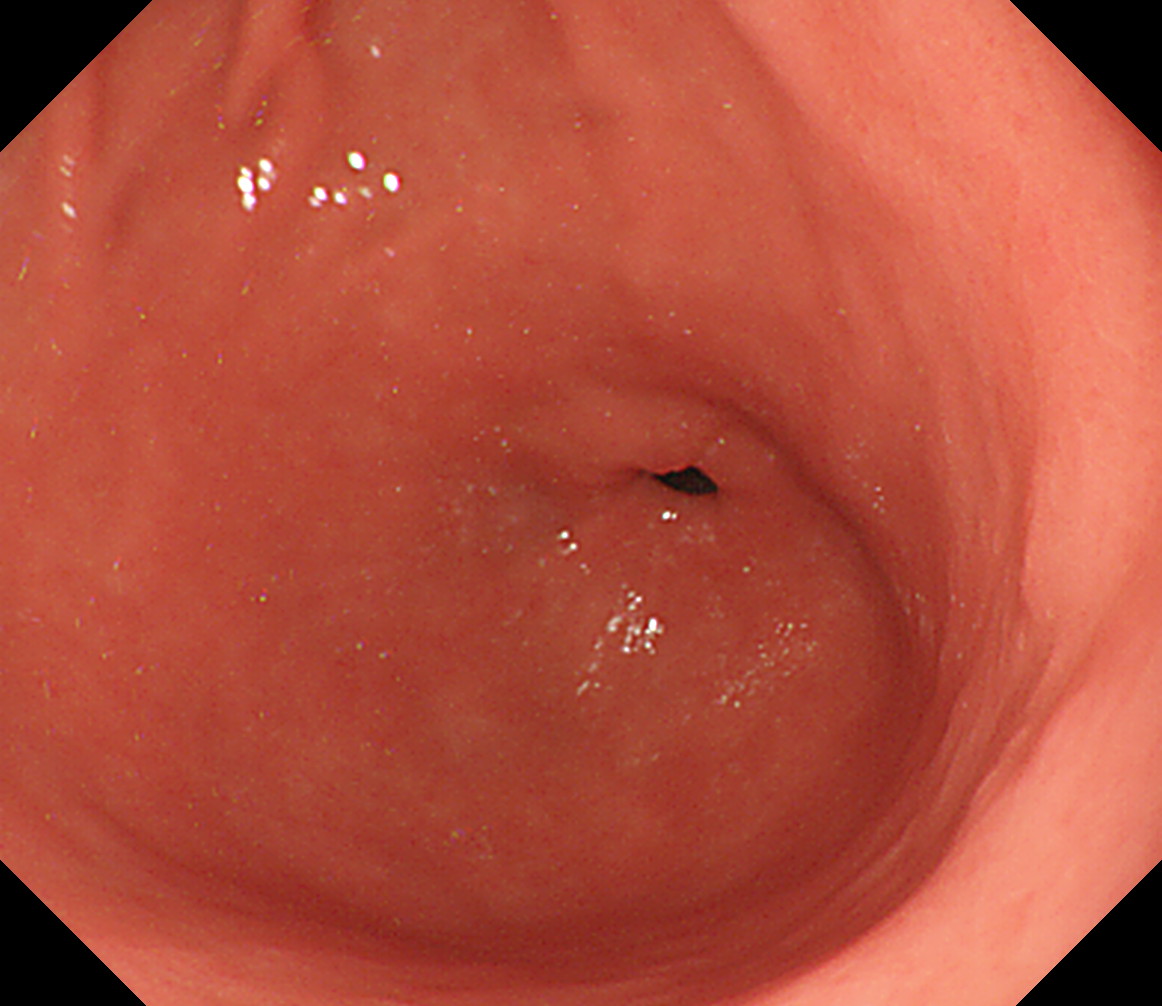

8 幽門輪 いわゆる「PーRing」 幽門輪

9 十二指腸球部前壁 十二指腸球部前壁